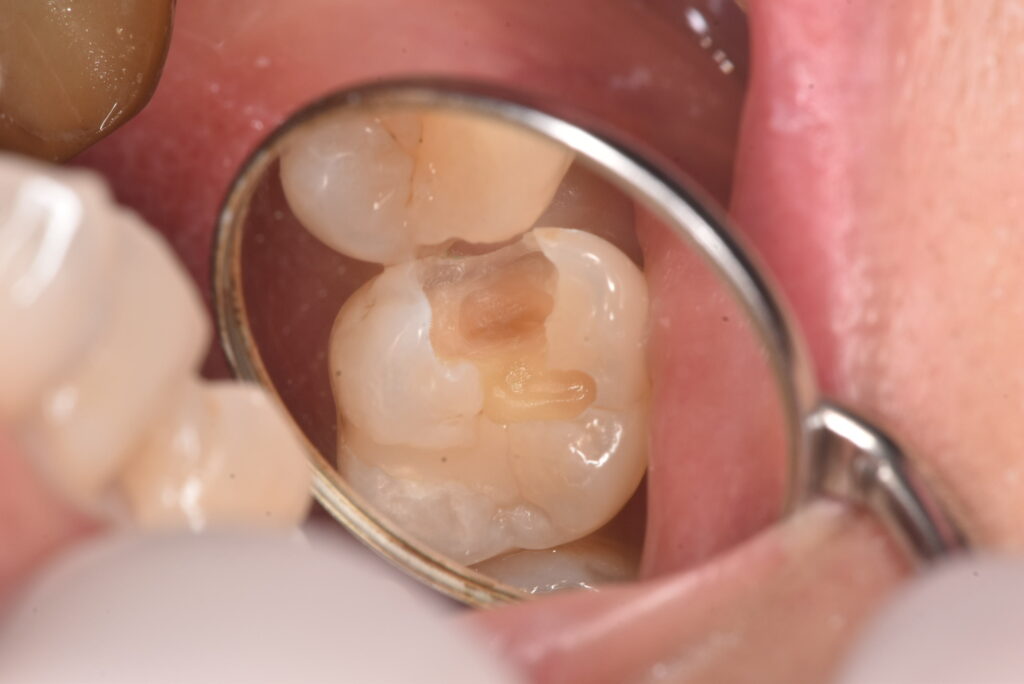

上の写真が処置した部位なります。写真からは、間に黒い部分があるのが見えると思いますが、レントゲン上ではどうでしょうか?

問題の部位は、ここになります。はっきりしたものは映っていません。では、その部分の実際はどうだったのかというと・・・

古いつめものの下の部分も含め、かなりの範囲に広がっていました。それよりも問題なのは、一番最後の写真に写っている削った部分の茶色い部分は、ほぼ神経の真横、ということです。そこまでの大きさなのかは、処置前には全く分かりませんでした。

この状態からは、歯の神経もとることになりえる、ということがお分かりかと思います。一番考えていただきたいこととして、最初の処置前写真から、最後の状態になることを想像できたでしょうか?ということです。

「痛みがなかったのに、歯医者でむし歯があると言われて、治療したら神経をとることになった。おかしい!」に対する回答の一つが上のケースになります。処置前は痛み等の症状はありませんでした。